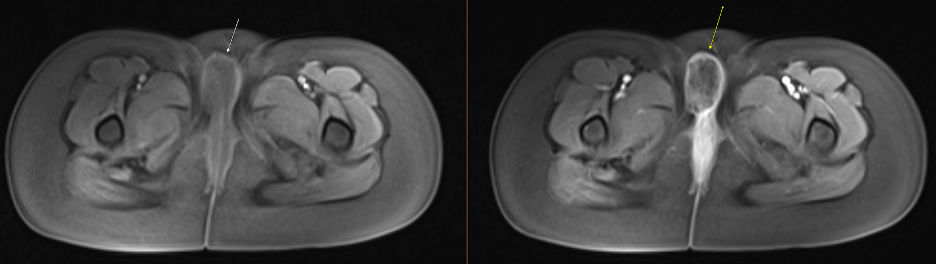

Diagnostic and laboratory testing. Contrast-enhanced MRI of the pelvis was obtained for better lesion characterization and surgical planning. MRI demonstrated a well-circumscribed, predominantly solid lesion with some cystic components, measuring 2.8 x 2.0 x 2.6 cm in the right labial region. The mass was homogenously hypointense on T1-weighted images and intermediate intensity T2-weighted images (Figure 1). Post-contrast imaging revealed heterogeneous, predominantly peripheral enhancement (Figure 2). Diffusion-weighted imaging (DWI) suggested high cellularity with diffuse diffusion restriction (Figure 3). T1 imaging suggested the absence of microscopic fat, hemorrhage, or calcifications (Figures 1 and 4). It appeared confined to the labia without deep pelvic infiltration. There were no suspicious satellite lesions or lymphadenopathy in imaging.

Figure 1. Pre (left) and Post-contrast (right) axial T1-weighted MR image reveals heterogeneous, predominantly peripheral enhancement of the lesion (arrow). Note the preserved tissue planes and absence of adjacent infiltration.